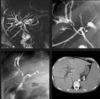

Telangiectasia Hemorrágica Hereditária ou Síndrome de Osler-Weber-Rendu (THH-OWR). ## Footnote Malformações vasculares intra-hepáticas (e pulmonares), com artérias ectasiadas e tortuosas, shunts; realce venoso precoce .

# Abdome: doença hepática difusa Telangiectasia Hemorrágica Hereditária ou Síndrome de Osler-Weber-Rendu (THH-OWR) ?

Doença genética autossômica dominante caracterizada por telangiectasias múltiplas e malformações arteriovenosas (MAV) em diversos órgãos.

# Abdome: doença hepática difusa Achados hepáticos da THH-OWR? (3)

1. Malformações vasculares intra e extra-hepáticas, com artérias ectasiadas e tortuosas; 2. Realce heterogêneo do parênquima hepático devido a telangiectasias e malformações AV; 3. Opacificação precoce das veias.

Colangite esclerosante primária (CEP). ## Footnote Irregularidade dos ductos biliares, com áreas de estenose alternando com dilatações. Na TC sinais de fibrose (doença avançada).

# Abdome: doença hepática difusa Colangite Esclerosante Primária (CEP)?

Doença crônica e progressiva que afeta os ductos biliares, causando inflamação, fibrose e eventual obstrução. É um processo autoimune, frequentemente associado a doenças inflamatórias intestinais.

# Abdome: doença hepática difusa **V ou F?** A CEP apresenta um curso característico com piora progressiva progressiva e aumento do risco de colangiocarcinoma.

Verdadeiro.

# Abdome: doença hepática difusa **V ou F?** Na imagem temos o aspecto de atrofia do fígado periférico e hipertrofia central (pseudotumor do lobo caudado), característico da CEP em estágio avançado.